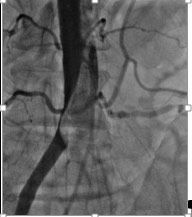

2084. На представленной ангиографии брюшного отдела аорты и подвздошного сегмента можно наблюдать